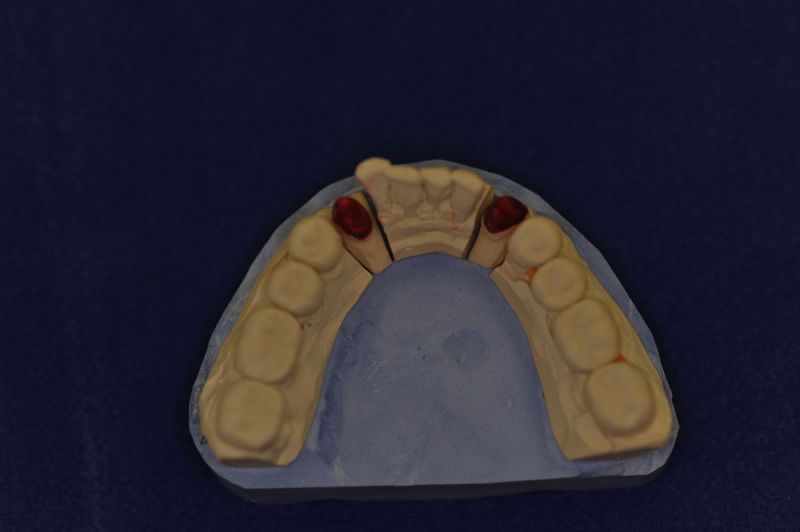

Der Patient erhält die beiden letzten Kronen zur Einstellung der dynamischen Okklusion.

In diesem Fall möglich über die Herstellung von zwei Eckzahnkronen